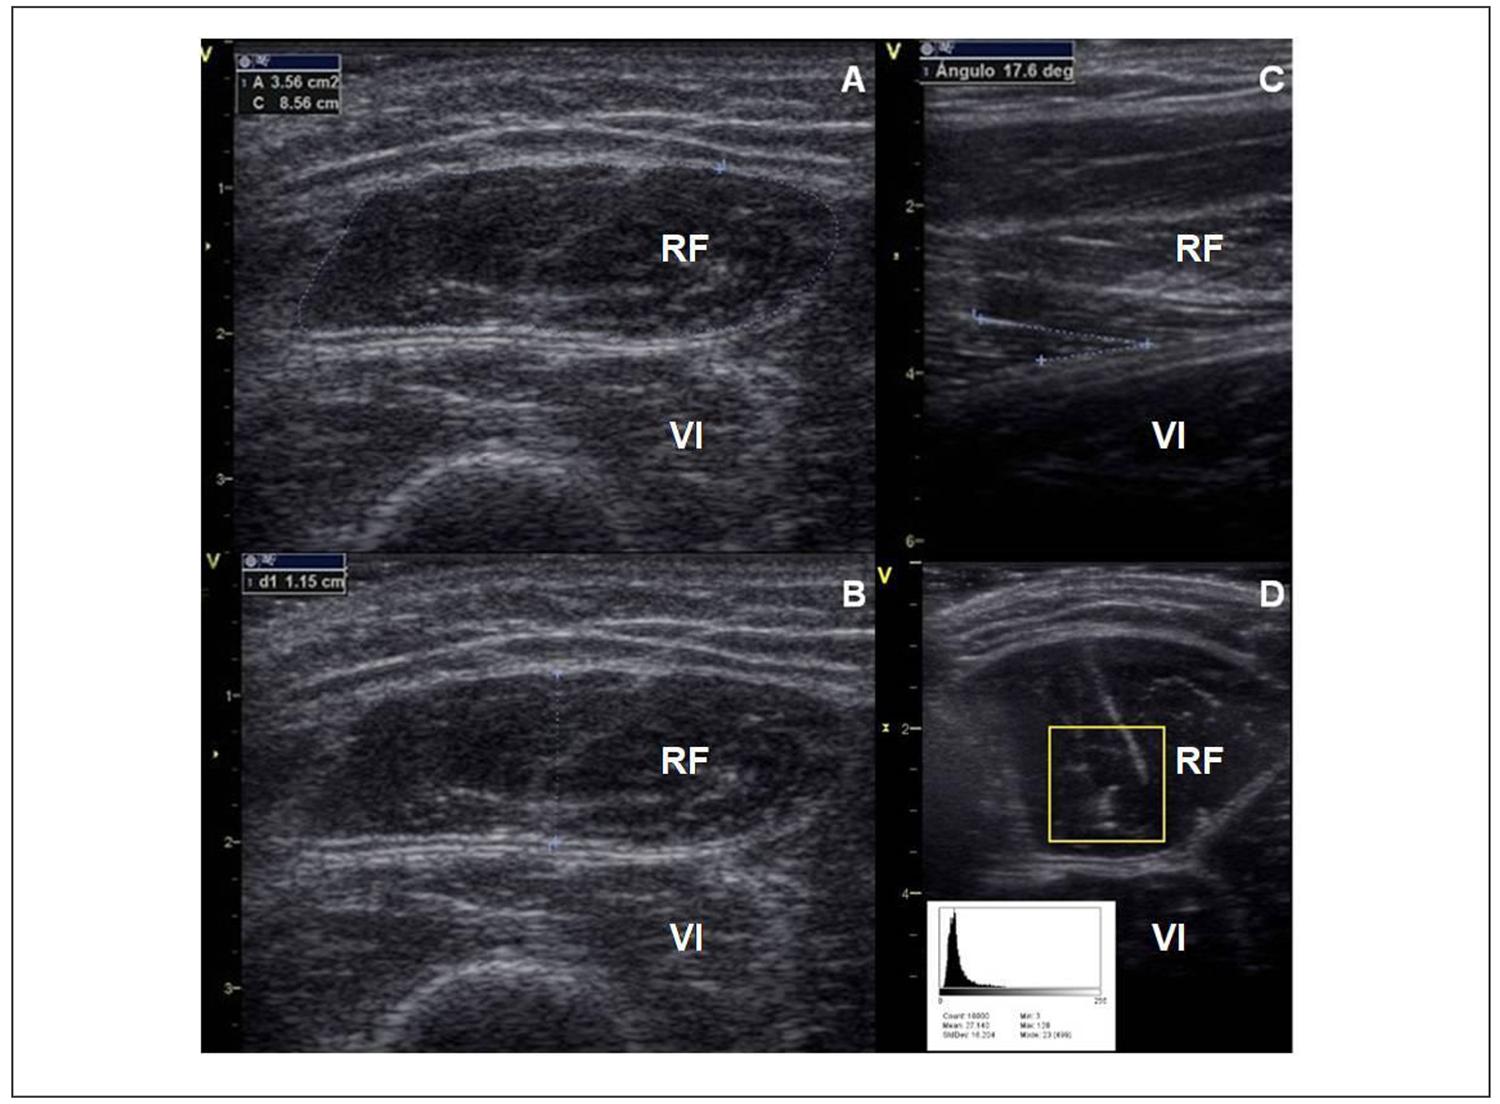

El grosor del compartimento muscular (GCP) se midió como la distancia entre la fascia superficial y la fascia profunda del músculo (o la membrana interósea en el antebrazo)6. Para el RF, también se midió el AST como el área dentro de la fascia muscular. El PA se obtuvo a partir de imágenes longitudinales como el ángulo formado por las fibras y la fascia muscular profunda7. Finalmente, la EI muscular se determinó mediante análisis asistido por software de la escala de grises de la imagen (ImageJ, NIH, Bethesda, MD)15 (Figura 1).